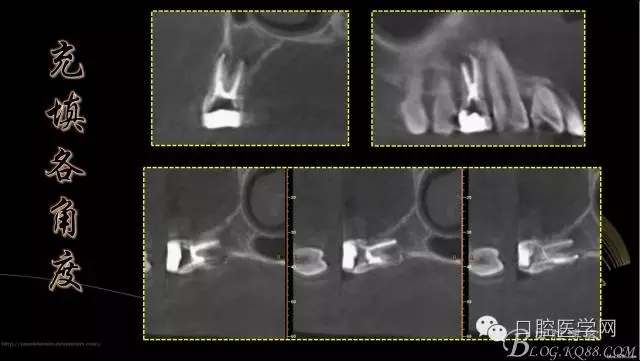

上頜第一前磨牙3根管